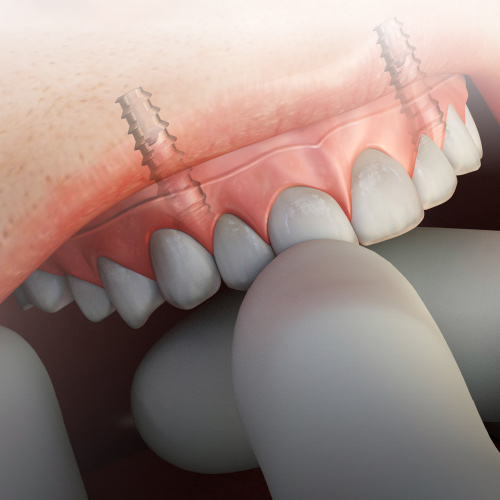

Dental Rehabilitation of the Atrophic Maxilla

Ankur Johri, DDS, MD, FACS

Friday, July 29, 2022

This Compendium eBook features a continuing education (CE) article presents important diagnostic and treatment planning principles of the All-on-4 treatment concept for the rehabilitation of the atrophic maxillary arch, and includes a case report illustrating free-hand implant placement using this treatment approach.